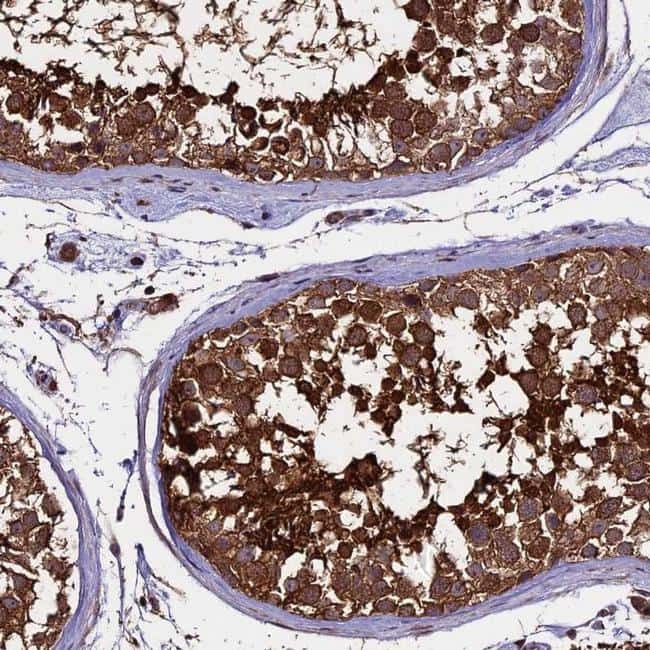

- Main image

- Experimental details

- Immunohistochemical analysis of PGPEP1L in human testis using PGPEP1L Polyclonal Antibody (Product # PA5-59726) shows strong cytoplasmic positivity in cells in seminiferous ducts.